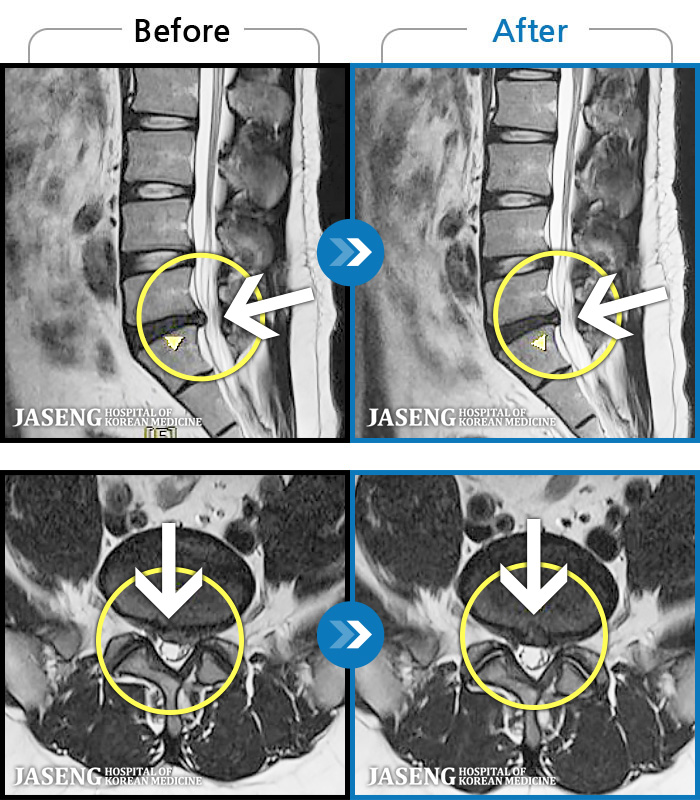

[뱸] 19.11.28~25.05.06

ȯںп Ǹ ǿ ԿǾ, ο ġ ۿ Ƿ ġḦ Ͻñ ٶϴ.